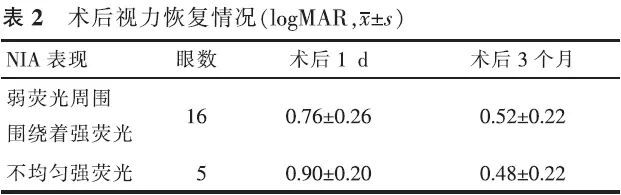

【摘要】 目的 近红外眼底自发荧光检查(NIA)联合OCT对孔源性视网膜脱离巩膜扣带术后早期黄斑结构的评估价值。方法 前瞻性系列病例研究。对21例(21眼)伴黄斑脱离的孔源性视网膜脱离患者行巩膜扣带术,于术后3个月行NIA及OCT检查。观察检查图像的异常和手术后视力的恢复情况。对视力的变化进行配对t检验,NIA与术后BCVA的相关性采用双向无序分类变量资料的关联性进行分析。结果 NIA:16眼表现为弱荧光周围围绕着强荧光,5眼表现为不均匀的强荧光。OCT:20眼存在黄斑下液;中心凹视网膜神经纤维层的厚度6眼变薄,14眼正常,1眼增厚;21眼IS/OS反射异常。视力恢复情况:术后3个月与术后1 d比较,NIA表现为弱荧光周围围绕着强荧光者,视力差异有统计学意义(t=9.922,P<0.05),NIA表现为不均匀强荧光者,视力差异无统计学意义(t=2.409,P>0.05),黄斑NIA表现与术后BCVA变化高度相关(C=0.502,P<0.05)。结论 孔源性视网膜脱离巩膜扣带术后早期,黄斑结构与功能均尚未完全恢复,需要我们加以重视。

【Abstract】 Objective To evaluate the changes in macular structure in the early stages after undergoing scleral buckling surgery for rhegmatogenous retinal detachment (RRD); to use melanin-related near-infrared fundus autofluorescence (NIA) combined with optical coherence tomography (OCT) for studing the changes. Methods This was a prospective case-series study. Melanin-related near-infrared fundus autofluorescence (NIA) and optical coherence tomography (OCT) examinations were performed on 21 patients with local primary RRD three months after undergoing a successful scleral buckling procedure for retinal reattachment. The RRDs in all 21 eyes involved the macula. To check the anomalies fo the images and the recovery of the vision after surgery. Changes invision after surgery were compared with a paired t test. The correlation of NIA and BCVA was analyzed with the relevance of two-way disorderly classification variable data. Results NIA revealed that 16 eyes had hypofluorescence surrounded by hyperfluorescence and 5 eyes had uneven hyperfluorescence. Submacular fluid was found in 20 eyes. The retinal nerve fiber layer in the central fovea became thinner in 6 eyes. In one eye, the retinal nerve fiber layer in the central fovea became thicker, and in another 14 eyes the thickness of the retinal nerve fiber layer was normal. The reflection from the photoreceptor inner and outer segment junction (IS/OS) was abnormal in all 21 eyes. Visual acuity measured with NIA revealed that the hypofluorescence which was surrounded by hyperfluorescence had improved at the 3-month follow-up compared to the 1-day follow-up examination (t=9.922, P<0.05), while VA measured at the same time revealed that uneven hyperfluorescence had not improved at the 3-month follow-up (t=2.409, P>0.05). The macular NIA results and the change in postoperative BCVA were highly correlated (r=0.502, P<0.05). Conclusion Macular function and structure do not fully recover in the early stages after undergoing scleral buckling to treat RRD. More attention should be paid to this problem.